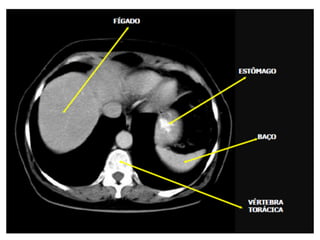

Tomografia do Abdome